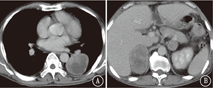

患者男,57岁,于2018年5月2日因"双侧颈部无痛性肿大淋巴结4个月"收入我院。既往吸烟史:吸烟30年,每天60支。入院查体:功能状态评分3分,双侧颈部触及多个肿大淋巴结,部分融合成团,最大直径约5 cm,质地硬,有压痛。左下肺呼吸音低,右侧腹部压痛,深触诊可触及肿物,大小6 cm×5 cm。左侧臀部可触及直径5 cm肿物。血常规:白细胞9.8×109/L,血红蛋白72 g/L,血小板677×109/L。肿瘤标志物:神经元特异性烯醇化酶21.91 ng/ml。肝肾功能及大、小便常规正常。骨髓穿刺活检:细胞形态未见异常,未见癌细胞;粒细胞、红细胞、巨核细胞增生活跃。颈部CT:鼻咽部未见异常,双侧颈部多发大小不等结节,考虑转移淋巴结。胸部CT:左肺下叶圆形软组织占位,边缘较光滑,未见分叶及毛刺,肿瘤大小63 mm×53 mm,内见坏死,增强扫描不均匀强化。纵隔肿大淋巴结,考虑转移。腹部CT:腹腔、双肾上腺肿物。右侧肾上腺明显,大小75 mm×53 mm,左侧肾下极与腰大肌分界不清,见图1。左侧臀部肿物,大小40 mm×51 mm,环周强化。颅脑磁共振成像、全身骨扫描未见异常。于2018年5月14日行左侧臀部切除活检:恶性肿瘤并坏死,免疫组织化学染色示:CKpan(+)、Vimentin(+)、CD3(-)、CD20(-)、CK7(-)、CK20(-)、Villin(-)、CK5/6(-)、P63(-)、NapsinA(-)、甲状腺转录因子-1(-)、Melan-A(-)、Melanoma(-)、CD30(-)、S100(-)、CD31(-)、Fli-1(-),不支持淋巴瘤、恶性黑色素瘤、血管源性肿瘤,不排除肉瘤样癌。2018年5月23日北京大学肿瘤医院会诊意见:支持肉瘤样癌。临床诊断:左肺肉瘤样癌伴颈部、纵隔、腹腔、盆腔淋巴结、双肾上腺、左臀部转移。输血治疗纠正贫血后于2018年6月5日开始口服安罗替尼抗肿瘤治疗(12 mg/d,第1~14天,21 d为1个周期)。2个周期后于2018年7月13日门诊复查颈部、胸、腹部CT:颈部、纵隔淋巴结较前略增大。左肺下叶肿块较前无明显变化,内见空洞。腹腔肿物较前略缩小,内见空洞。右侧肾上腺肿物较前略增大,内见空洞。左侧肾上腺肿物较前略增大,见图2。按照实体瘤疗效评价标准(RECIST)1.1版评价疗效为病情稳定。现继续安罗替尼靶向治疗中。